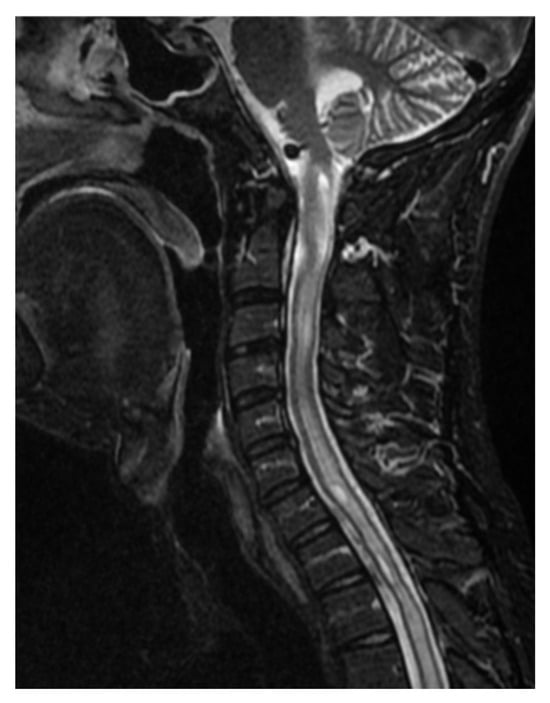

Case Report